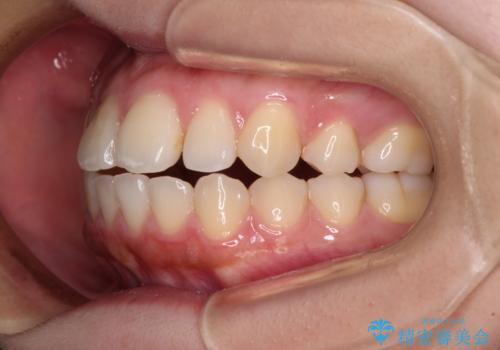

再矯正 開咬に後戻りした歯列をインビザラインで改善

- 矯正治療の後戻りを気にして来院された患者様です。

デコボコと上下前歯の隙間が気になるものの、しっかりと治療をしたいという意思はないとのことで、インビザラインの中でもアライナー数に制約のあるライトパッケージを用いて、治療できる範囲まで歯列を改善していくこととしました。

インビザラインは前歯部の開咬に効果的であることが多く、ライトパッケージにもかかわらず、十分満足のいく仕上がりとなりました。